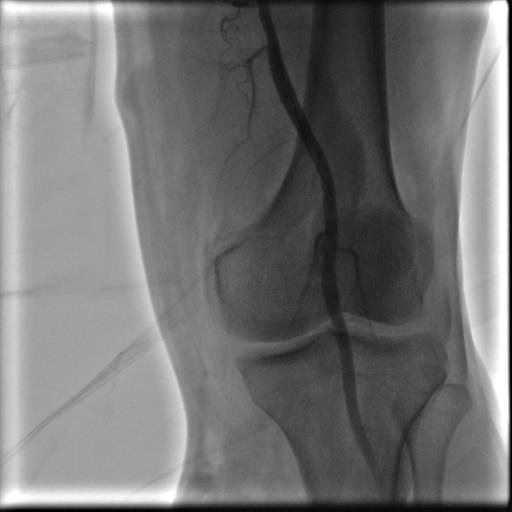

Yürürken bacak ağrısı olan ve ayak parmaklarında iyileşmeyen yaraları olan hastanın yapılan tetkiklerinde bacak damarlarının diz üstü ve diz altı tıkalı olduğu tespit edildi.Anjio da balon ve stent işlemiyle damarları açıldı. Hastamız şu an sağlıklı bir şekilde hayatına devam etmektedir.